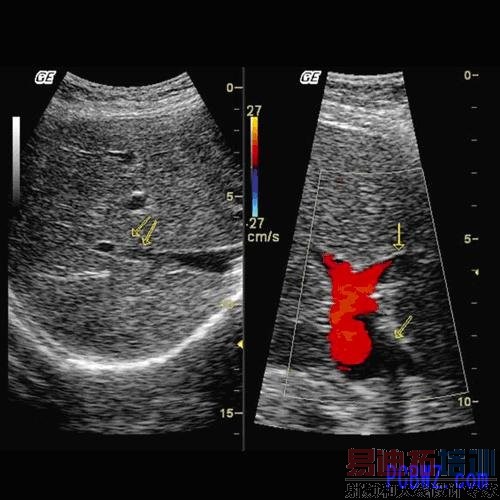

2. 多普勒影像(Doppler)-- 多普勒模式 (Doppler mode) 是通过跟踪回波的频率偏移来探测物体在各种环境中运动的速度。这些原理被应用在检查体内血液或者其它液体在体内流动的情形。这种技术是透过发射一连串声波进入体内,然后对反射波进行快速傅利叶转换(Fourier Transform, FFT)处理。这种计算处理方法即可确定来自人体的讯号频率分量,以及它们与流体速度的关系。

3.静脉和动脉模式 -- 这种方式是将多普勒影像与灰度模式的联合应用。通过处理多普勒位移产生的音效讯号即可获得速率与节律。